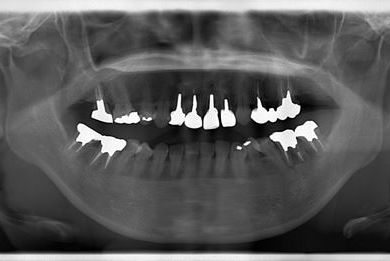

| 性別/年齢 | 女性 / 38歳 | ||||||||||||||||||||||||||||||||

| 主訴 | 奥歯の痛み(虫歯)。銀歯の所だと思います。なるべく痛くない治療がいいです。 | ||||||||||||||||||||||||||||||||

| 治療方針 | セラミック治療にて、審美的回復を行う。 | ||||||||||||||||||||||||||||||||

| 治療内容 | ハイブリッドセラミッククラウン1本(ハイブリッドセラミック用土台1本) | ||||||||||||||||||||||||||||||||

| 総治療費 | 96,600円 | ||||||||||||||||||||||||||||||||

| 治療期間 | 2ヶ月 |